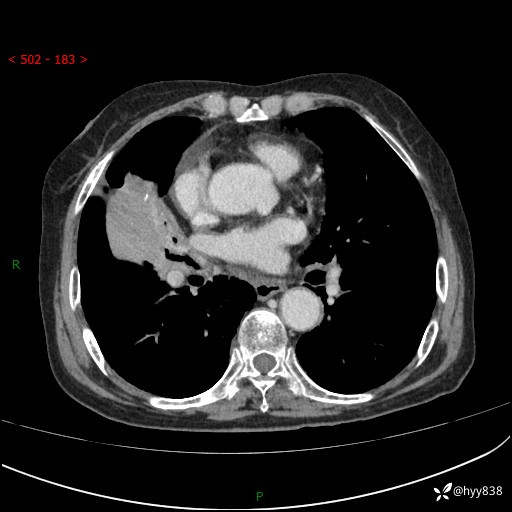

胸部CT增强(外院平扫)